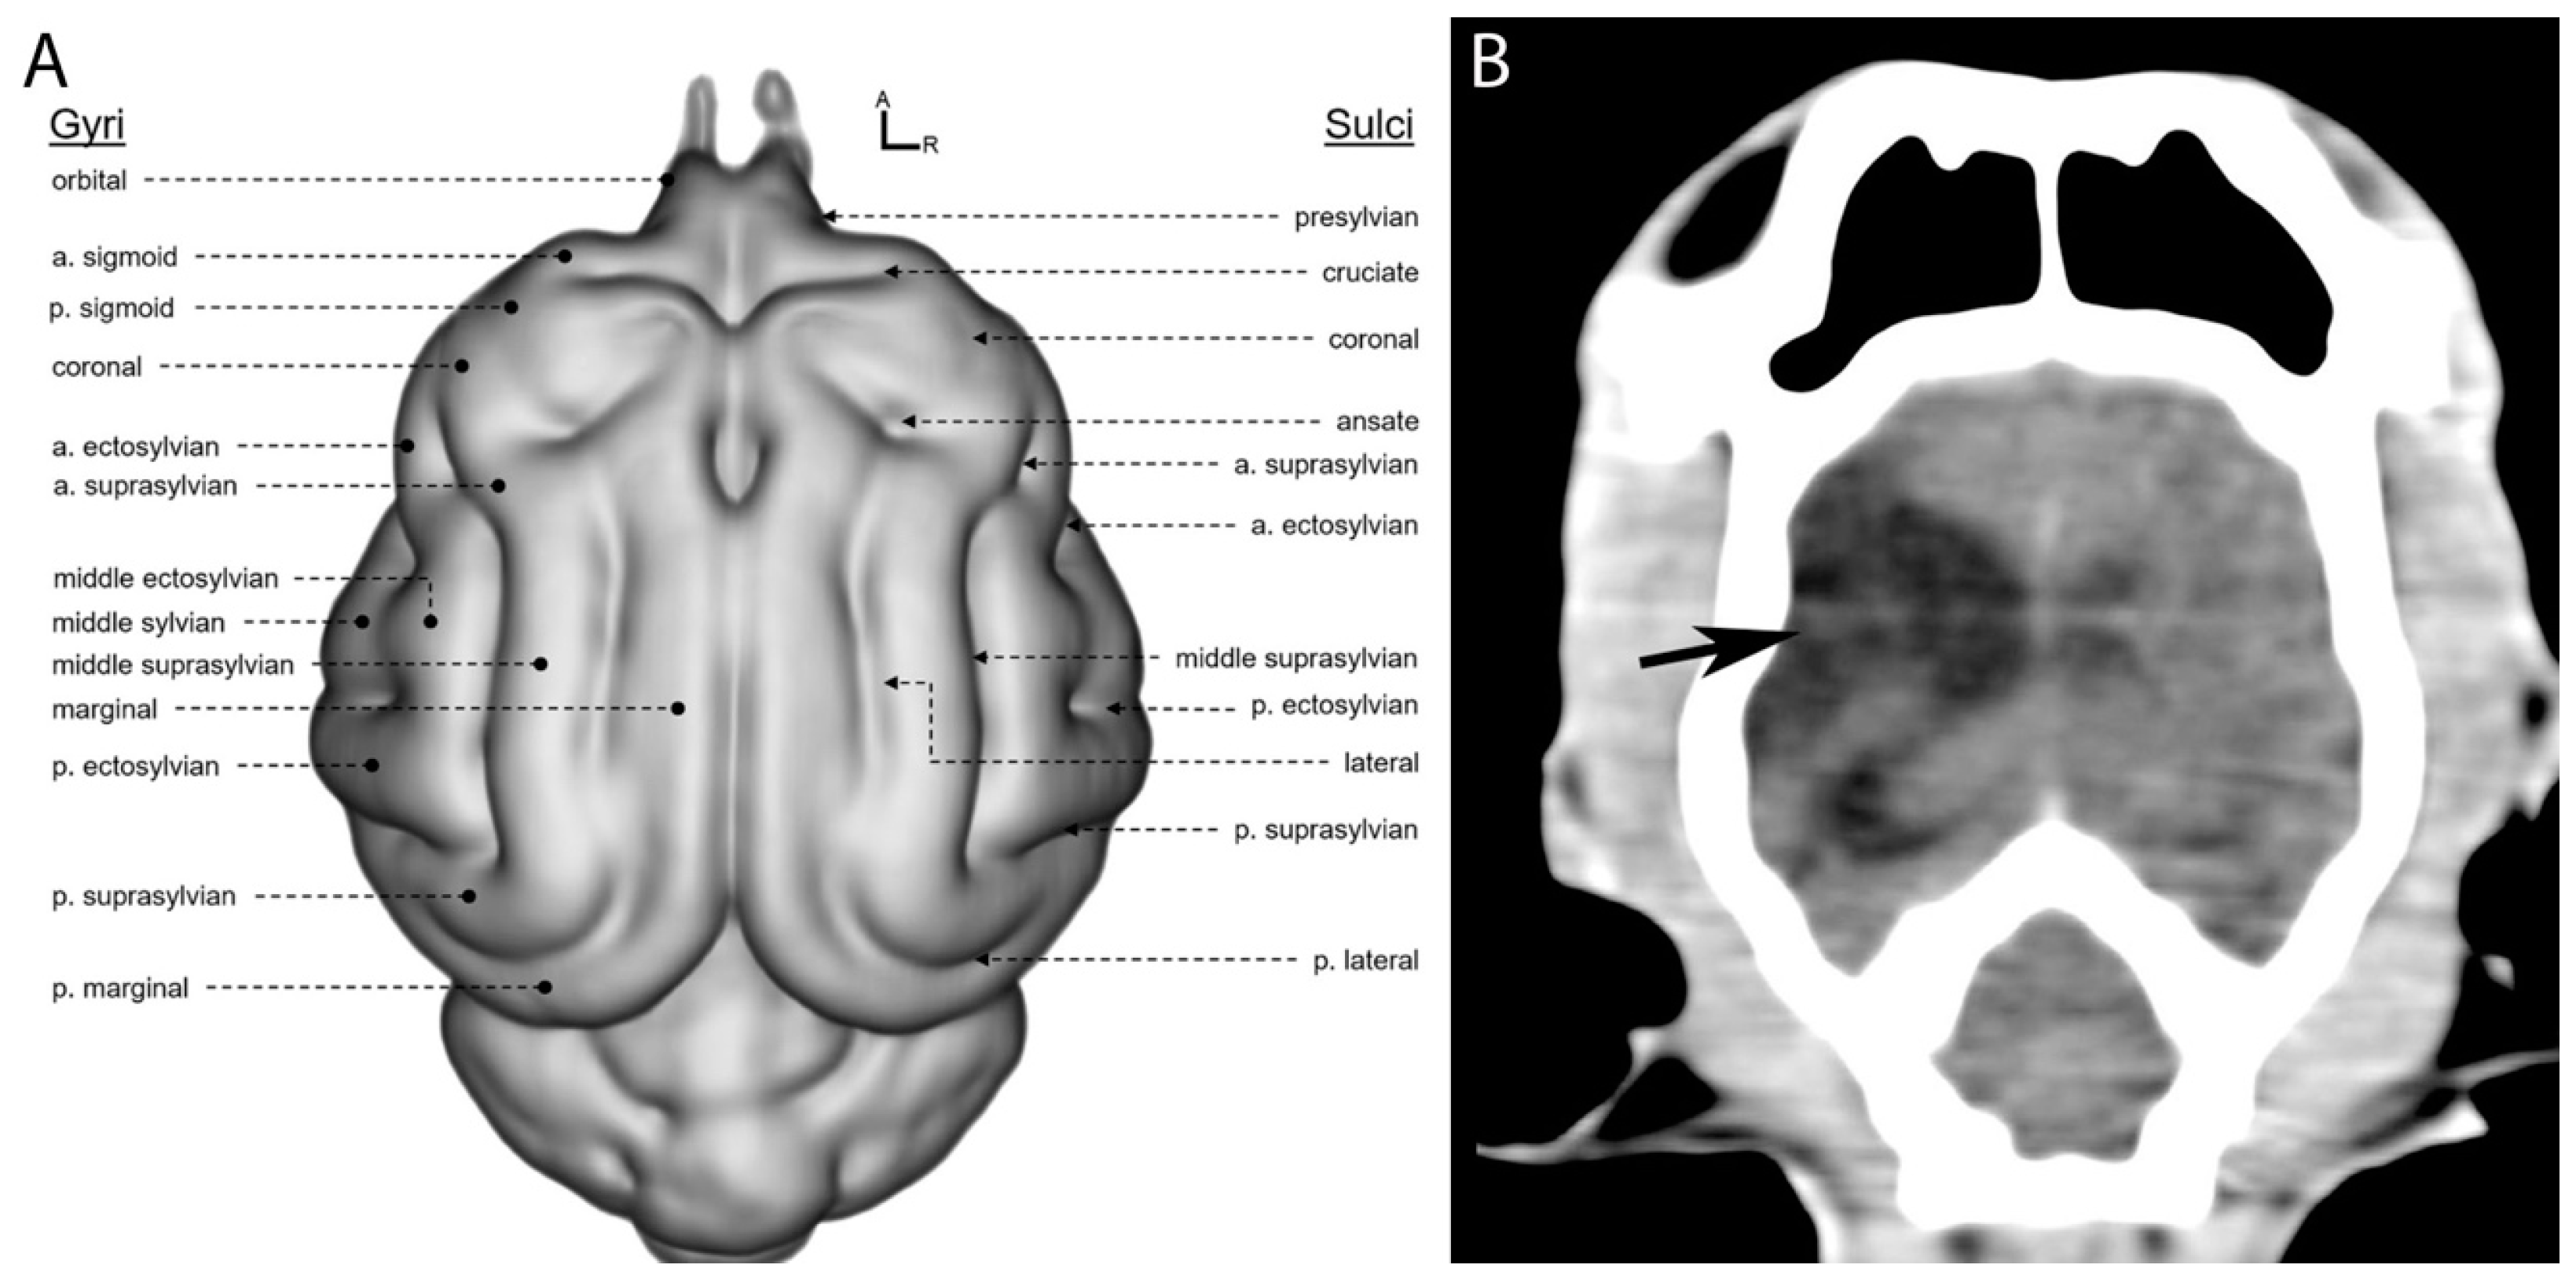

The approximate location of brain lobes in carnivores can be determined based on the position of the corresponding frontal, parietal, and occipital bones of the calvaria. These cerebral lobes are typically situated directly beneath the bones of the same name. However, distinguishing these bones is often challenging in imaging, particularly in transverse CT scans [10]. The hypodense areas observed in the right hemisphere on the CT scan correspond anatomically to regions primarily involving the frontal and parietal lobes (Figure 3), as shown in the anatomical diagram (Figure 3A). Specifically, the lesions were presumed to be located in the anterior suprasylvian gyrus and middle ectosylvian gyrus (part of the frontal lobe) and the posterior suprasylvian sulcus (part of the parietal lobe).

Figure 3. Coronal view of the feline brain. (A) Anatomical features of the gray matter of the cat brain and (B) a dorsal view of the CT scan of the patient (original). Source: (A) Stolzberg et al., 2017 [20], modified.